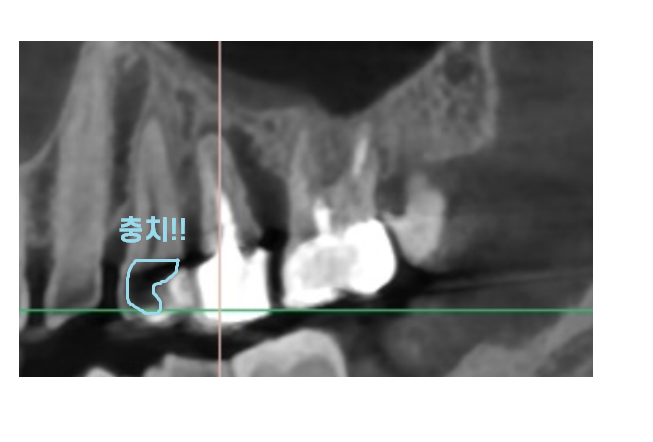

ct를 찍어보았는데

왼쪽 위에 문제 치아가

뼈가 많이 녹았습니다.

ct상 문제가 되는

뼈가 많이 녹은 치아 1개만 발치를 말씀드렸는데요.